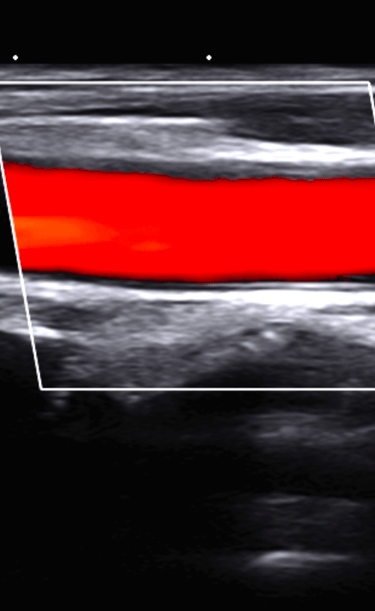

Por el costo de una ecografia, aprovechando nuestros conocimientos, experiencia y tecnologia te exploramos el abdomen total, el tiroides y carotidas

ECOGRAFIA O ULTRASONIDO DE TODO EL CUERPO

Ultrasonido y Densitometría

Estudios de ultrasonido y densitometría para un diagnóstico completo y detallado.

Ultrasonido o Ecografia

APLICA PARA : CABEZA, CUELLO, TORAX, ABDOMEN Y EXTREMIDADES

PARA TODAS LAS ESPECIALIDADES

PIONEROS CON MAS DE 40 AÑOS DE EXPERIENCIA

REALIZADA POR EXPERTOS

Galería Médica

Explora nuestros servicios de radiología y medicina regenerativa.